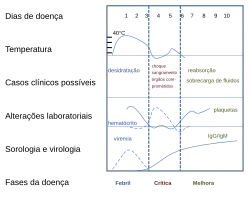

Os sintomas característicos da dengue são febre de início súbito, dor de cabeça (normalmente localizada atrás dos olhos), dores musculares e articulares, além de erupções cutâneas. O nome alternativo para a dengue, "febre quebra-ossos", vem da dor causada em músculos e articulações.[12][19] O curso da infecção é dividido em três fases: febril, crítica e de recuperação.[20]

A fase febril envolve febre alta, potencialmente acima de 40 °C, associada a dor de cabeça e dor generalizada; esta fase geralmente dura de dois a sete dias.[19][20] Podem também ocorrer vômitos.[9] A erupção ocorre em 50 a 80% dos pacientes[19][21] no primeiro ou no segundo dia de sintomas, como pele corada, ou mais tarde no curso da doença (dias 4-7), como uma erupção morbiliforme, (semelhante a causada pelo sarampo).[21][22] Algumas petéquias (pequenas manchas vermelhas que não desaparecem quando a pele é pressionada, as quais são causadas por ruptura de capilares) podem aparecer nesta fase,[20] assim como algum sangramento leve da membrana mucosa da boca e do nariz.[17][19] A febre em si é classicamente de natureza bifásica, depois é interrompida e, em seguida, volta durante um ou dois dias, embora muitas vezes haja grande variação na forma como este padrão realmente acontece em cada pessoa.[11][22]

Em algumas pessoas, a doença prossegue para uma fase crítica logo após o período de intervalo da febre[9] e, normalmente, durando de um a dois dias.[20] Durante esta fase, pode haver acumulação significativa de fluido nas cavidades torácica e abdominal, devido ao aumento da permeabilidade e do vazamentos dos capilares sanguíneos. Isto leva à depleção de fluido a partir da circulação e hipoperfusão, a diminuição do fornecimento de sangue para os órgãos vitais.[20] Durante esta fase, pode ocorrer a disfunção de órgãos e sangramentos graves, normalmente a partir do trato gastrointestinal.[17][20] SCD (síndrome do choque da dengue) e hemorragias (dengue hemorrágica) ocorrem em menos de 5% de todos os casos de dengue.[17] No entanto aqueles que tenham sido previamente infectados com outro sorotipo do vírus da dengue ("infecção secundária") têm um risco aumentado.[17][23] Essa fase crítica, apesar de rara, geralmente ocorre mais em crianças e em adultos jovens.[9] A febre hemorrágica da dengue (FHD) e a síndrome de choque da dengue (SCD) atingem pelo menos 500 mil pessoas todos os anos e apresentam uma taxa de mortalidade de até 10% para pacientes hospitalizados e de 30% para pacientes que não receberam tratamento.[6]

A fase de recuperação ocorre em seguida, com a reabsorção do líquido que vazou para a corrente sanguínea.[20] Isso geralmente dura de dois a três dias.[17] A melhora é muitas vezes surpreendente e pode ser acompanhada por grave coceira e por uma frequência cardíaca lenta.[17][20] Outra erupção pode ocorrer, seja maculopapular ou vasculítica, que é seguida por uma descamação da pele.[9] Durante esta fase, pode ocorrer um estado de sobrecarga de líquidos que, se afetar o cérebro, pode causar um redução do nível de consciência ou convulsões no paciente.[17] A sensação de fadiga pode durar algumas semanas em adultos.[9]

A primeira alteração detectável em exames laboratoriais é uma baixa contagem de células brancas do sangue, o que pode ser seguido por baixo nível de plaquetas e acidose metabólica.[17] Níveis moderadamente elevados de aminotransferase (AST e ALT) a partir do fígado são comumente associados com a baixa de plaquetas e de células brancas do sangue.[9] No estágio grave da doença, os resultados indicam de fuga de plasma em hemoconcentração (como indicado por um aumento dos hematócritos) e hipoalbuminemia.[17] Derrames pleurais ou ascites podem ser detectadas por meio de exame físico quando grandes,[17] mas a demonstração de fluido no ultrassom pode auxiliar na identificação precoce da síndrome de choque da dengue.[12][17] O uso de ultrassom é limitado pela falta de disponibilidade em muitas regiões.[12] A síndrome de choque da dengue está presente se a pressão arterial cai para ≤20 mm Hg, juntamente com o colapso vascular periférico.[9] O colapso vascular é determinado em crianças através de recarga capilar atrasada, aumento da frequência cardíaca ou extremidades frias.[20]

Estes testes de laboratório são apenas de valor diagnóstico durante a fase aguda da doença , com exceção da sorologia . Os testes de anticorpos específicos do vírus do dengue, tipos IgG e IgM, podem ser úteis na confirmação de um diagnóstico nas fases mais avançadas da infecção. IgG e IgM são produzidos depois de entre 5 e 7 dias. Os níveis mais altos de IgM são detectados após uma infecção primária, mas o IgM também é produzido na reinfecção. O IgM se torna indetectável entre 30 e 90 dias após a infecção primária, mas após reinfecções. IgG, pelo contrário, permanece detectável por mais de 60 anos e, na ausência de sintomas, é um indicador útil de infecções anteriores. Depois de uma infecção primária, o IgG atinge níveis de pico no sangue após 14-21 dias. Em re-infecções subsequentes, os níveis de pico são geralmente mais elevados. IgG e IgM proporcionam imunidade protetora para o serótipo do vírus infectante.[19][24] O teste de laboratório para os anticorpos IgG e IgM podem reagir de forma cruzada com outros Flavivírus e podem resultar em um falso positivo após infecções recentes ou vacinas com o vírus da febre amarela ou a encefalite japonesa.[9] A detecção de IgG sozinho não é considerada um diagnóstico, a menos que as amostras de sangue sejam coletadas há 14 dias e seja detectado um aumento maior do que quatro vezes nos níveis de IgG específico. Numa pessoa com sintomas, a detecção de IgM é considerada um diagnóstico.[16]